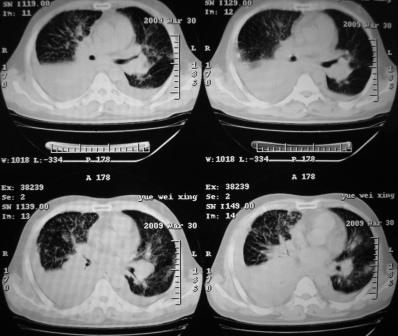

xx 男 43岁

右下叶支气管变窄闭塞,右下叶实变,双肺野弥漫性斑片状影,肺纹理增多增粗,纵隔多发淋巴结肿大,双侧胸水,考虑1双肺继发型结核,右下叶支气管内膜结核,双侧胸水2右下叶中央型肺癌伴右下叶实变,双肺转移,纵隔淋巴转移,双侧胸腔积液3淋巴瘤,请结合病史进一步检查。

病史呢?先考虑----右中央型肺癌继发下叶不张,双肺及纵隔淋巴转移,双侧胸腔积液,心包积液。

不排除---心脏病变所致

右肺下叶支气管中断闭塞,右下肺见不规块影,并胸腔积液,考虑肺中央型肺癌继发下叶不张,\\双侧胸腔积液,心包积液。

考虑右中央型肺癌并下叶不张,双侧胸腔积液,心包积液

右侧中央型肺癌伴右肺下叶不张,双肺及纵隔淋巴转移,双侧胸腔积液,心包积液。

1)考虑右侧中央型肺癌伴右肺下叶不张,双肺及纵隔淋巴转移。2)双侧胸腔积液,以右侧为甚。3)心包积液。